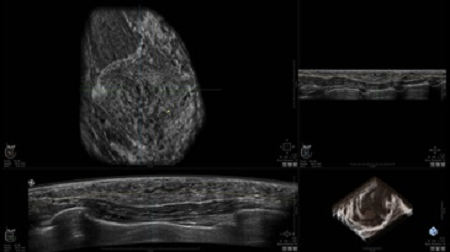

GE INVENIA ABUS – это современный УЗИ аппарат, который создан для точной и эффективной диагностики сканирования с высокой плотностью молочных желез. Выявляемость патологий раковых и предраковых стадий заболевания составляет 55%, что в конечном счете позволяет ставить врачу точные и своевременные диагнозы. Традиционные методы использования маммографии не показывают такой выявляемости, ограничиваясь лишь 3-38%.

УЗИ-аппарат GE INVENIA ABUS позволяет проводить максимально операторонезависимые процедуры, что значительно снижает риск неправильной постановки диагноза и сопутствующие издержки на обработку информации. Система готовит отчет в течение 3-х минут после сканирования, это безусловное преимущество по сравнению с обычным УЗИ сканером.

• датчик с изогнутой апертурой для качественного исследования

• сканирование одной грудной железы в трех проекциях не более 60 сек.;

• обработка результатов за три минуты.

Возможности встроенной УЗ-системы:

• Увеличение или уменьшение степени сжатия грудной железы;

• Функция автоматического сканирования активируется одним нажатием;

• Возможность отмены сканирования;

• Глубина проникновения УЗ-лучей – до 50 мм;

• Одно детализированное изображение можно получить менее чем за 1 минуту

• Многорядная светодиодная подсветка;

• Встроенный сверхширокий вогнутый датчик С15-6ХW.